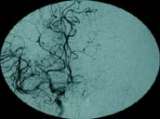

fig. 1: BEFORE the procedure: an angiograph showing the connecting vessels of the right to the left side at the base of the brain only allowed some flow into the first portion of the left middle cerebral artery, but the remainder was blocked.

A perfusion MRI study was conducted and determined the area of the impaired blood flow, figure 2 shows the left middle cerebral artery territory, the white area is where the blockage occur; here, the connecting vessels of the right to the left side at the base of the brain only allowed some flow into the first portion of the left middle cerebral artery (fig. 1).